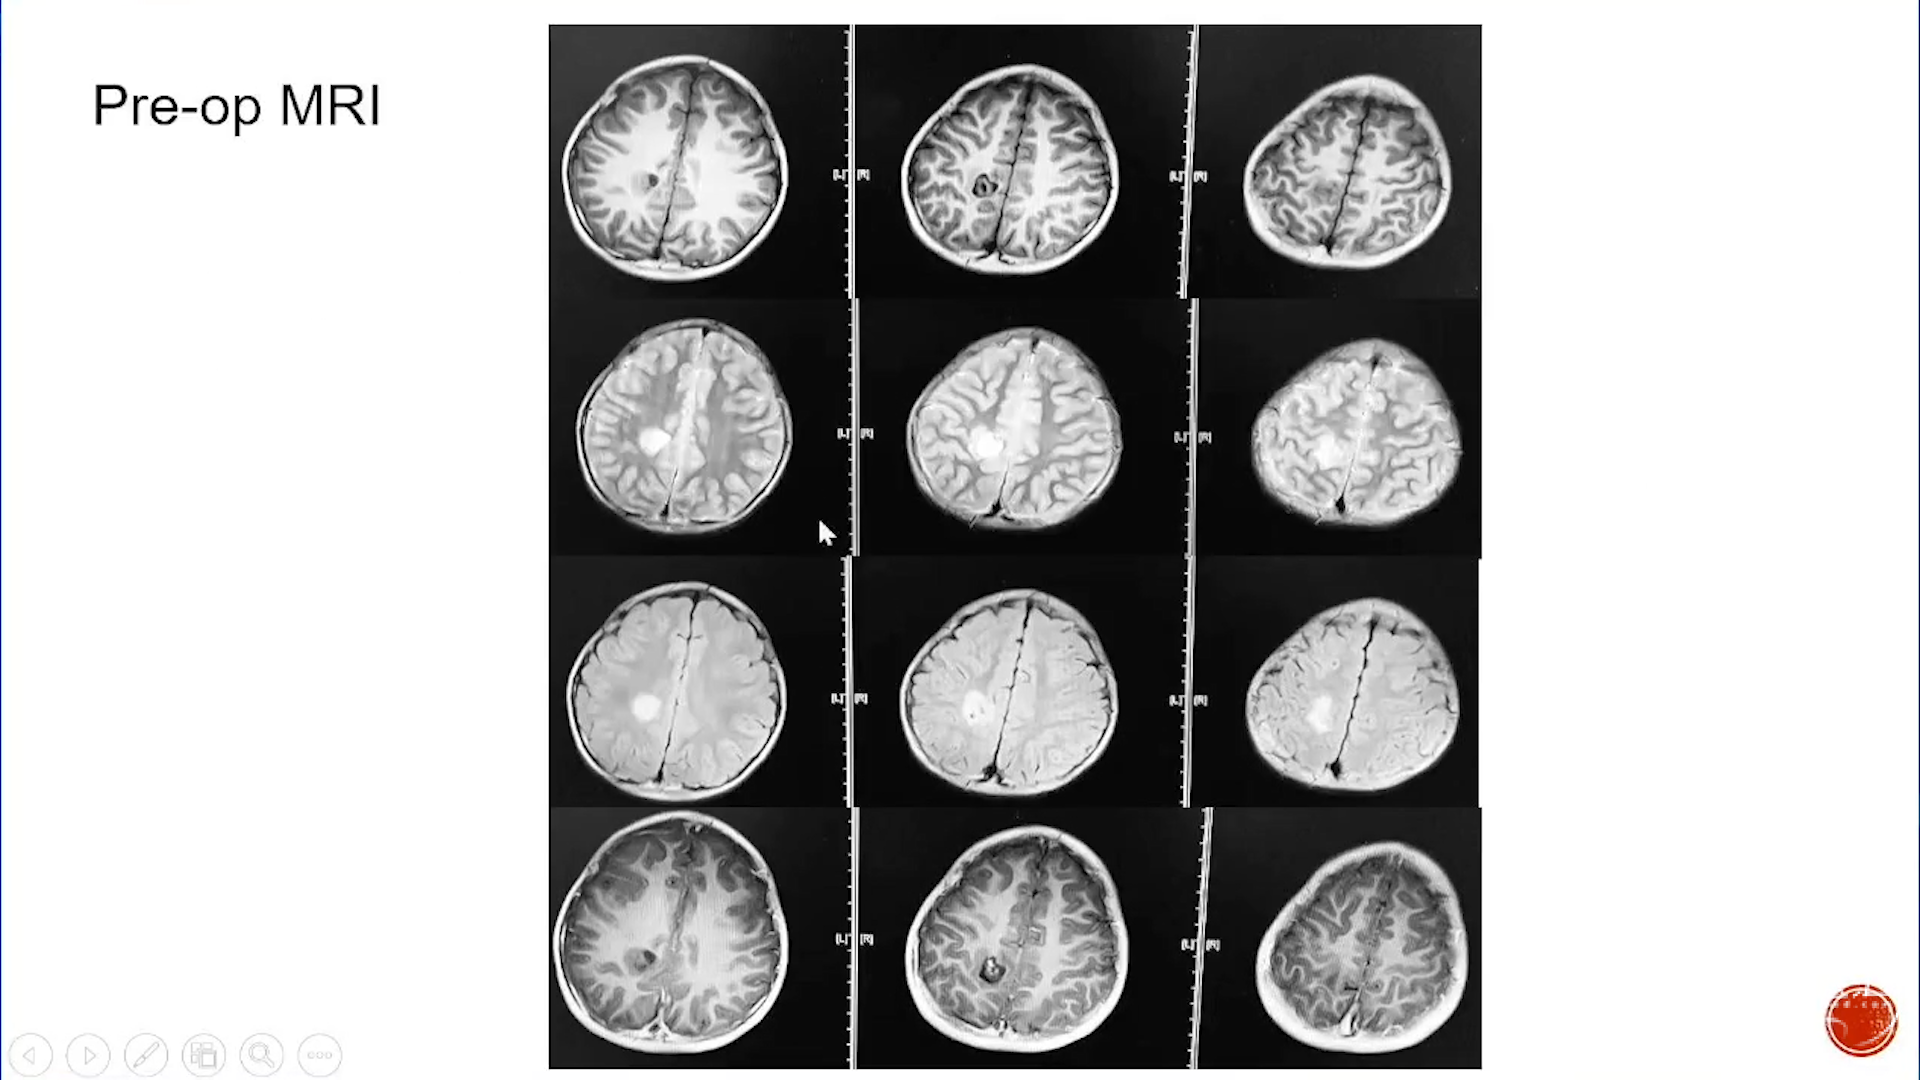

大脑半球儿童低级别胶质瘤